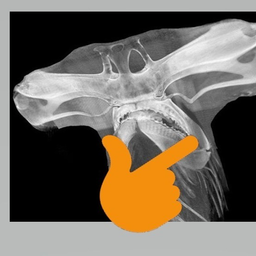

Живет у моих родителей такой красавец. Зовут Мурза (Мурзиком не солидно будет, все таки ветеран кошачьих боев). Мамка его пока жива была всех окрестных котов гоняла (родители живут в поселке). Он как подрос, продолжил ее дело. Бывало на пару недель гулять уходил.

В боях конечно получал раны, но морда всегда довольная была когда возвращался

Сейчас родители его особо не выпускают на улицу, берегут - один глаз он потерял, вторым сейчас наполовину видит только.